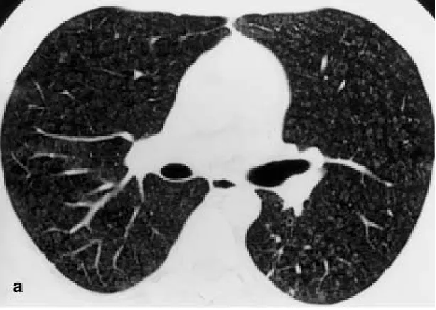

斑片状肺泡浸润影(典型COP

多灶性实变影